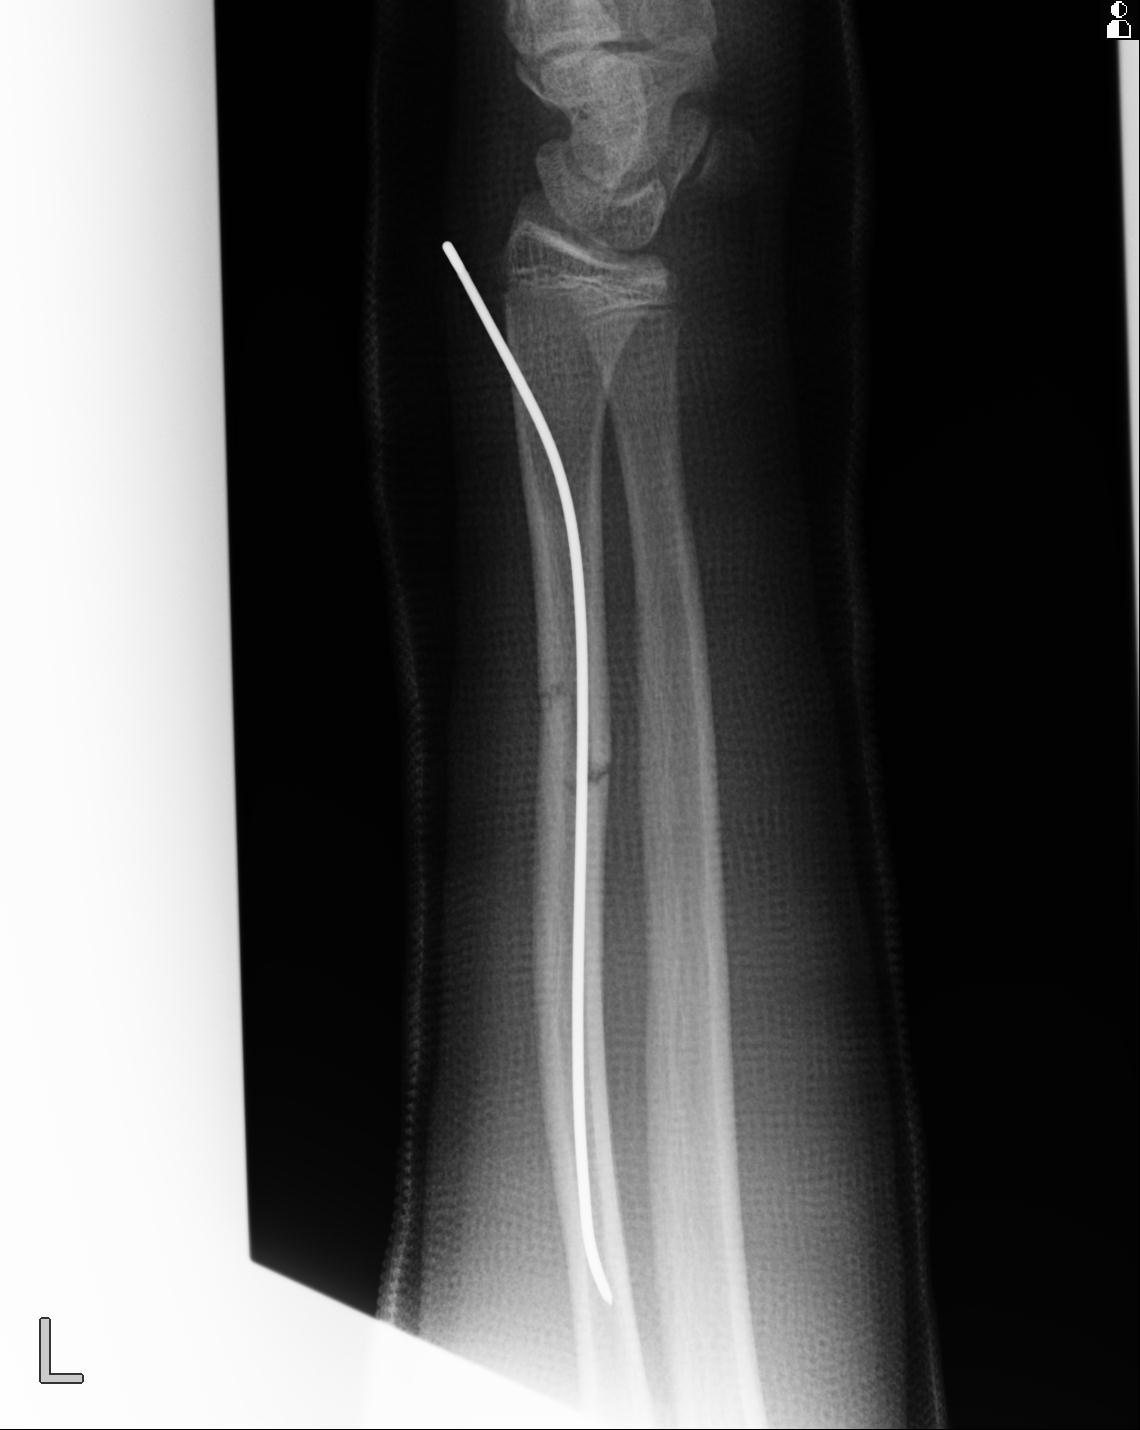

110211 1/6 1/8 左前腕 4R 15歳男性 橈骨骨幹部骨折